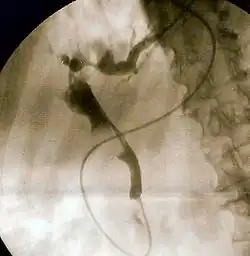

- Colangiopancreatografía retrógrada endoscópica. Confirma la obstrucción y el nivel, permite la recolección de especímenes para su cultivo y citología, es la indicada para el diagnóstico si la ultrasonografía y la tomografía axial computarizada no han sido concluyentes. Puede ser indicada como parte de la terapéutica.[1][4][2]